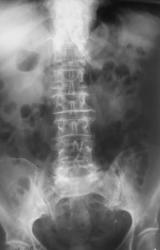

Пациентка, находящаяся на лечении в хирургическом отделении направлена на рентгенологическое исследование почек и мочевыводящих путей – внутривенную урографию, с «дежурным диагнозом» - «Почечная колика».

Пациентка подготовлена к исследованию не то, что неудовлетворительно - в кишечнике значительное количество газа, который весьма «массивно» накладывается на область почек и мочевыводящих путей, а отвратительно, что в последнее время весьма часто имеет место быть, и вынуждает сотрудников рентгеновского отделения прибегать к исследованию в условиях нефротомографии, что приводит, как к увеличению дозы облучения на пациента, так и  удлинению времени исследования.

Иллюстрация 1. На обзорной рентгенограмме области почек и мочевыводящих путей теней характера конкрементов не выявлено. Контуры поясничных мышц не дифференцируются. В поясничном отделе позвоночника определяются явления дистрофического характера в виде межпозвонкового остеохондроза, деформирующего спондилёза и деформирующего спондилартроза. Имеет место незначительная ротация тел отдельных поясничных позвонков, визуализируется формирование правостороннего, умеренно выраженного правостороннего сколиоза, по всей видимости, дискогенного характера. В области малого таза с обеих сторон определяются плотноватые тени по типу очаговых, возможно тени флеболитов и тени значительной плотности, приближающиеся к «костной» и «известковой» плотности, возможно, тени конкрементов, возможно мягкотканые окостенения.